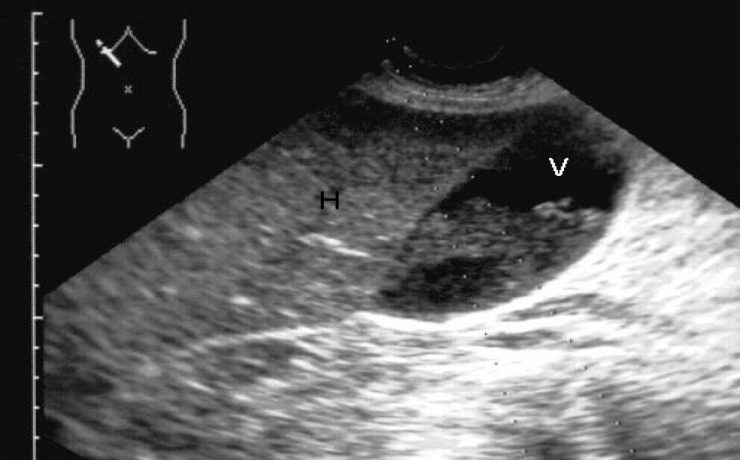

El incremento de la obesidad, del síndrome metabólico y su subsiguiente manifestación hepática, el hígado graso no alcohólico, se ha convertido en una enfermedad muy común en la práctica médica. El desarrollo de los conocimientos sobre el NASH se basa en la teoría inicial de los dos golpes o momentos.